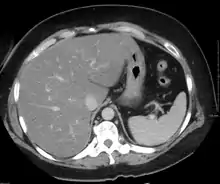

Medical imaging

On X-ray computed tomography (CT), the increased fat component will decrease the density of the liver tissue, making the image less bright. Typically the density of the spleen and liver are roughly equivalent. In steatosis, there is a difference between the density and brightness of the two organs, with the liver appearing darker.[11] On ultrasound, fat is more echogenic (capable of reflecting sound waves). The combination of liver steatosis being dark on CT and bright on ultrasound is sometimes known as the flip flop sign.